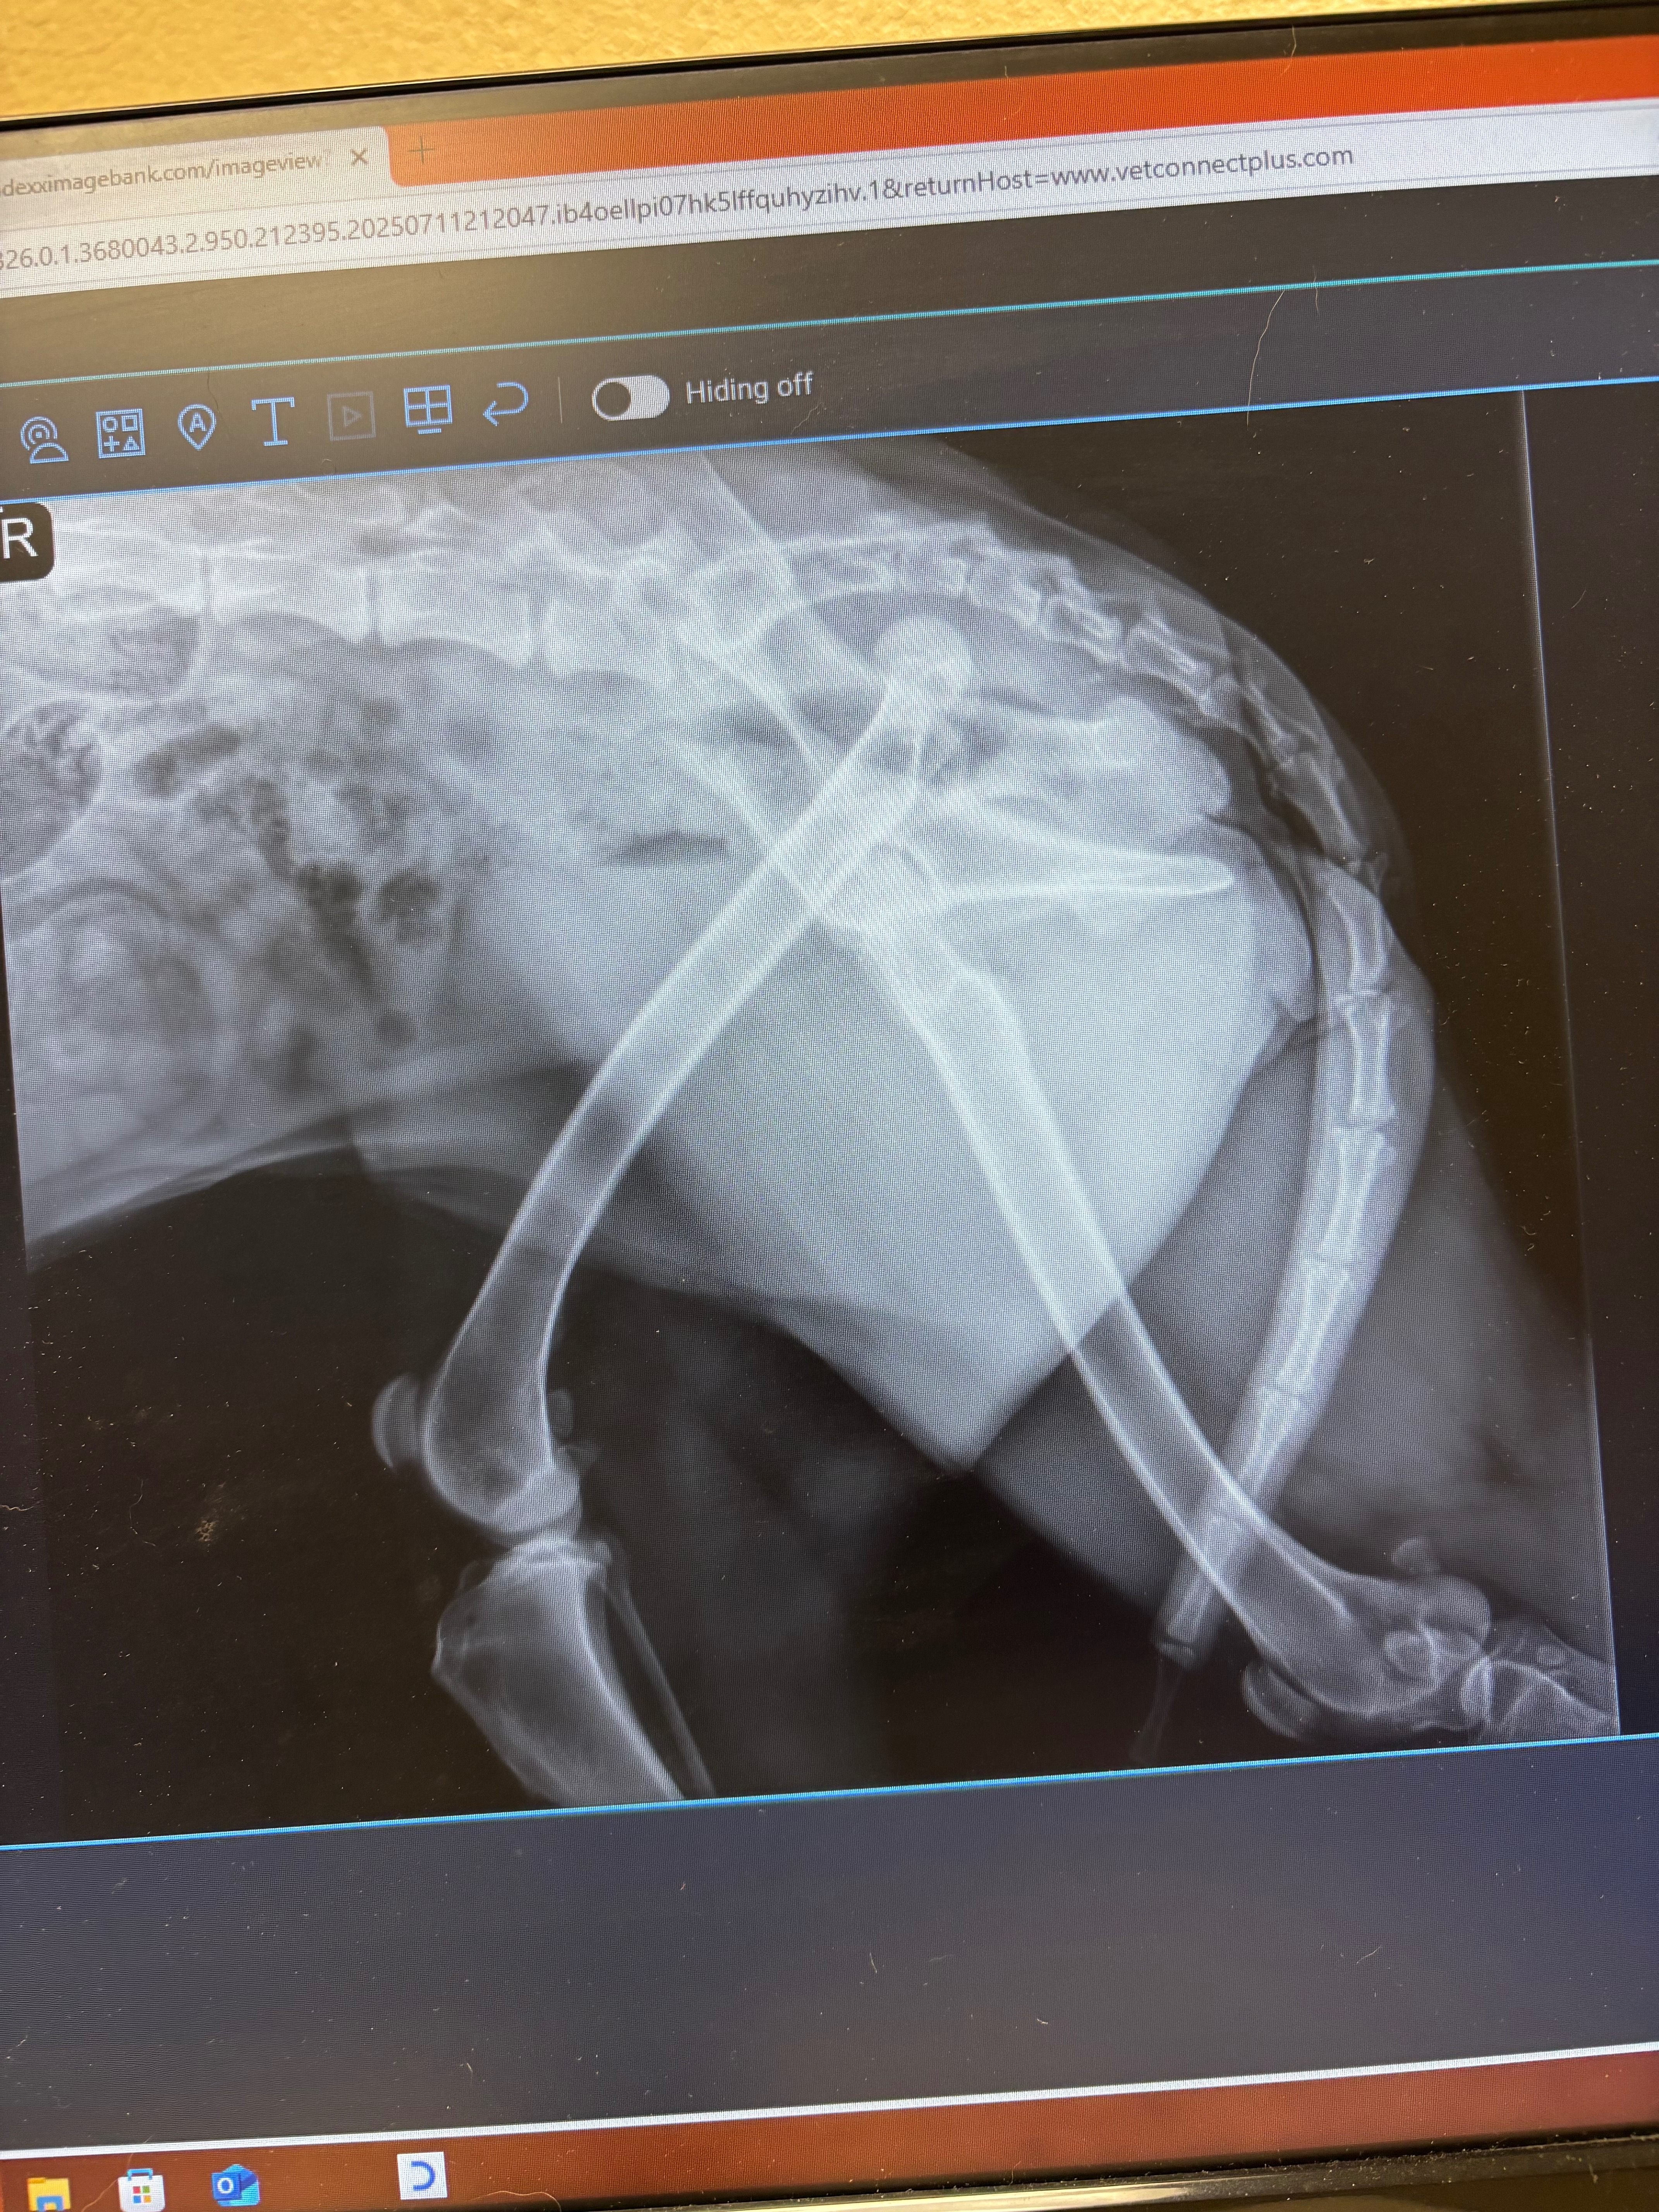

Rueger lives for the outdoors. She’s happiest when she’s running free, ears flopping, tail wagging, soaking up the sunshine. But in a heartbreaking turn of events, Rueger recently suffered a severe hip injury that now requires emergency surgery—a procedure that wasn’t planned for, and has come with an overwhelming financial burden.